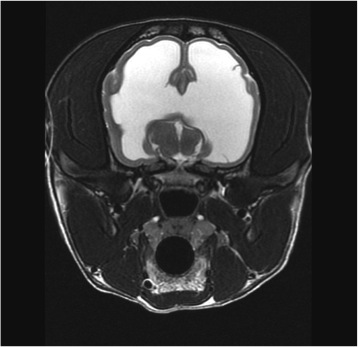

Transverse T2